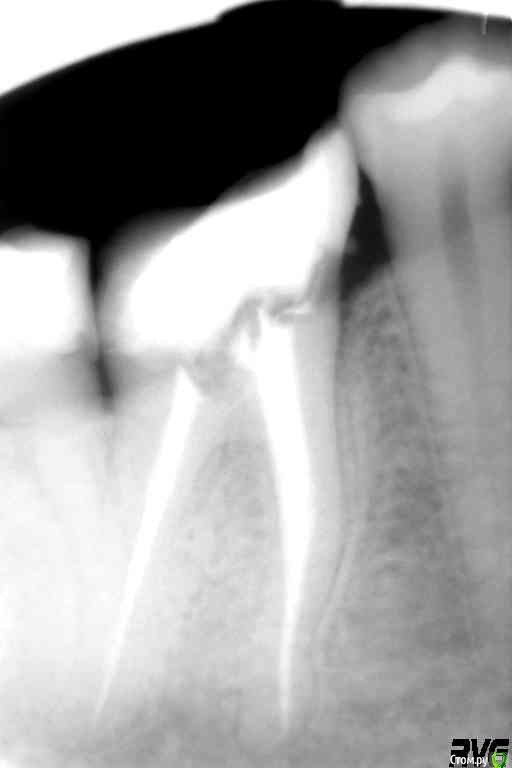

Джастина Опубликовано 2 ноября, 2020 Автор Поделиться Опубликовано 2 ноября, 2020 Вот рентген до заделки каналов: Вот после: Ссылка на комментарий

Evikrol Опубликовано 2 ноября, 2020 Поделиться Опубликовано 2 ноября, 2020 Ваш доктор все правильно сделал, по рентгену до видно что зуб был сильно разрушен, коронка обязательна. Хотите самым современным материалом, то ищите доктора кто сделает керамическую реставрацию с адгезивной фиксацией. Удалить один нерв была бы ошибка, так делать нельзя. Каналы вам шикарно запломбировали. 2 Ссылка на комментарий